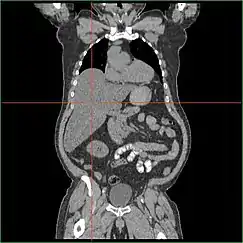

Hepatomegaly

Impairment in the liver's ability to perform gluconeogenesis leads to clinically apparent hepatomegaly. Without this process, the body is unable to liberate glycogen from the liver and convert it into blood glucose, leading to an accumulation of stored glycogen in the liver. Hepatomegaly from the accumulation of stored glycogen in the liver is considered a form of non-alcoholic fatty liver disease. GSD I patients present with a degree of hepatomegaly throughout life, but severity often relates to the consumption of excess dietary carbohydrate. Reductions in the mass of the liver are possible, since most patients retain residual hepatic function that allows for the liberation of stored glycogen at a limited rate.

GSD I patients often present with hepatomegaly from the time of birth. In fetal development, maternal glucose transferred to the fetus prevents hypoglycemia, but the storage of glucose as glycogen in the liver leads to hepatomegaly. There is no evidence that this hepatomegaly presents any risk to proper fetal development.

Hepatomegaly in GSD type I generally occurs without sympathetic enlargement of the spleen. GSD Ib patients may present with splenomegaly, but this is connected to the use of filgrastim to treat neutropenia in this subtype, not comorbid hepatomegaly. Hepatomegaly will persist to some degree throughout life, often causing the abdomen to protrude, and in severe cases may be palpable at or below the navel. In GSD-related non-alcoholic fatty liver disease, hepatic function is usually spared, with liver enzymes and bilirubin remaining within the normal range. However, liver function may be affected by other hepatic complications in adulthood, including the development of hepatic adenomas.